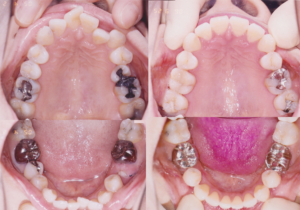

画像説明 :

①主訴 : 上の前歯の並びが悪い

②診断名あるいは主な症状 : 左下第二小臼歯の歯冠崩壊を伴う叢生

③年齢 : 36歳1ヶ月

④治療に用いた主な装置 : エッジワイズ・セラミック装置

⑤抜歯部位 : 上下顎左右第二小臼歯

⑥治療期間 : 1年5ヶ月

⑦治療費概算(外税) : 初診料 ¥5,000 診断料 ¥50,000 初診料 ¥720,000 処置料 ¥7,000

⑧リスク副作用 : 所見無し